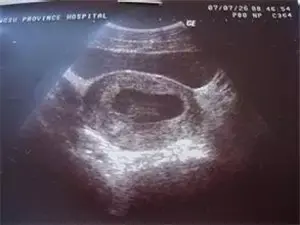

原则上在孕40天时,我们就可以通过阴道超声,观察到宫内的孕囊,在孕45天时,看到胚芽和胎心搏动。

如果此时血清HCG >1000 IU ~ 1500 IU,B超还没有看到宫内的典型孕囊,就基本肯定异位妊娠的诊断,需要留院观察,动态超声检查,看输卵管和其它部位是否出现孕囊和胎心。

因此,在这个怀孕阶段,不要拒绝超声检查,即使HCG的检测水平只有几百单位, B超没有见到宫内孕囊,都要密切观察是否宫外孕可能。